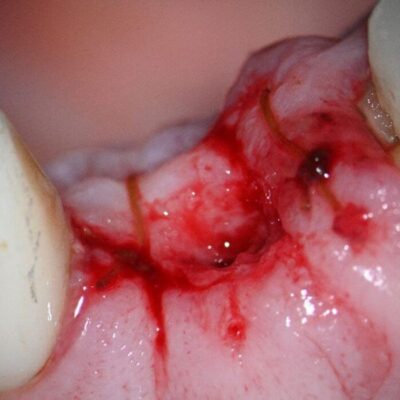

As the implant was placed by Dr. K. about 8 years ago, he was referred there for recovery of the fractured zirconia abutment and abutment screw. Recovery of fractured zirconia abutments from Ankylos implants are almost always difficult and tricky due to the tight conical connection at 5.7 degrees and the hardness of the zirconia. Because the abutment screw is free floating (the through bore is smaller than the threads), this presents an additional roadblock to recovery. Evidently, the patient was seen for about 1.5 hours, and while not excessive in my experience, there was only partial recovery of the fractured components. On examination, it was clear while some of the conical portion of the zirconia abutment had been removed, so had some of the implant top. The decision was made to proceed with finishing the recovery as I felt the remaining portion of the conical connection was enough to provide a stable abutment to implant connection. As the area had been flapped the previous day the proximal sutures were left intact and only a small amount of tissue contouring was needed to provide adequate access to visualize the implant top. The site was photographed prior to proceeding with further recovery efforts. As the screw head had already been removed along with the top two thirds of the conical abutment, the bottom portion of the conical abutment was concentrically removed with a surgical length high speed round diamond under microscope visualization. This was done to the level of the indexing splines which start approximately 3mm below the top of the implant. At that time, the zirconia splines became visible, and several small chunks of zirconia were retrieved. With careful manipulation of the screw fragment with an endodontic explorer and modified endodontic spoon, the screw was mobilized and maneuvered so a surgical length ¼ round bur could be placed on the screw outside diameter (OD), in an open implant spline. Again, with microscope guidance, the screw fragment was recovered along with the remaining zirconia fragments. The implant was cleaned, and the supplied healing abutment was placed finger tight. The recovery was completed without further damage to the implant. The patient’s existing provisional was modified to fit the healing abutment contours and was recemented with Tempbond clear, as it appeared to be the cement that was previously used. The patient was dismissed to return to Dr. S. for continuation of his restorative treatment plan.